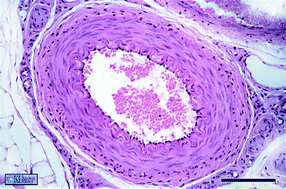

Interfaces are ubiquitous in nature and absolutely key for life as illustrated by such complex interfaces as the cell membrane and the endothelial and epithelial linings of tissues. The mechanical properties of these interfaces play an important role in their biological functions. In this highlight, we describe our recent work (Pocivavsek et al., Science, 2008, 320, 912) using geometry as a tool for studying the behavior of complex interfaces. General scaling laws emerging from studying the shape of elastic interfaces can in turn be used in their characterization. Interfacial wrinkling is a well known phenomenon, however, the geometric patterns seen at biological interfaces are often far from idealized sinusoidal wrinkles. We show how more complex and non-linear patterns naturally emerge from wrinkles and how material properties can be extracted from these non-linear geometries.